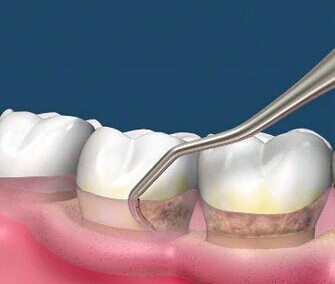

早期牙齿松动,主要是进行牙齿洁治(洗牙)、龈下刮治去除牙齿周围的牙石、菌斑等引起炎症的东西,以减轻牙齿周围的炎症。

(龈下刮治可有效去除牙菌斑,缓解牙周病)